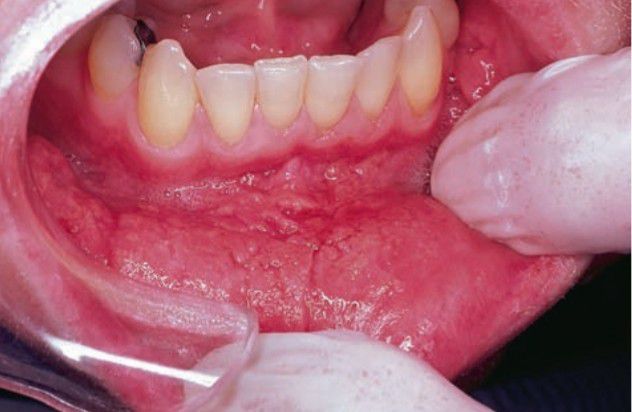

Pyostomatitis vegetans

The cause of pyostomatitis vegetans is unknown, although it may be seen in association with ulcerative colitis, spastic colitis, chronic diarrhea, and Crohn’s disease. More than 25% of cases are not associated with gastrointestinal disturbance